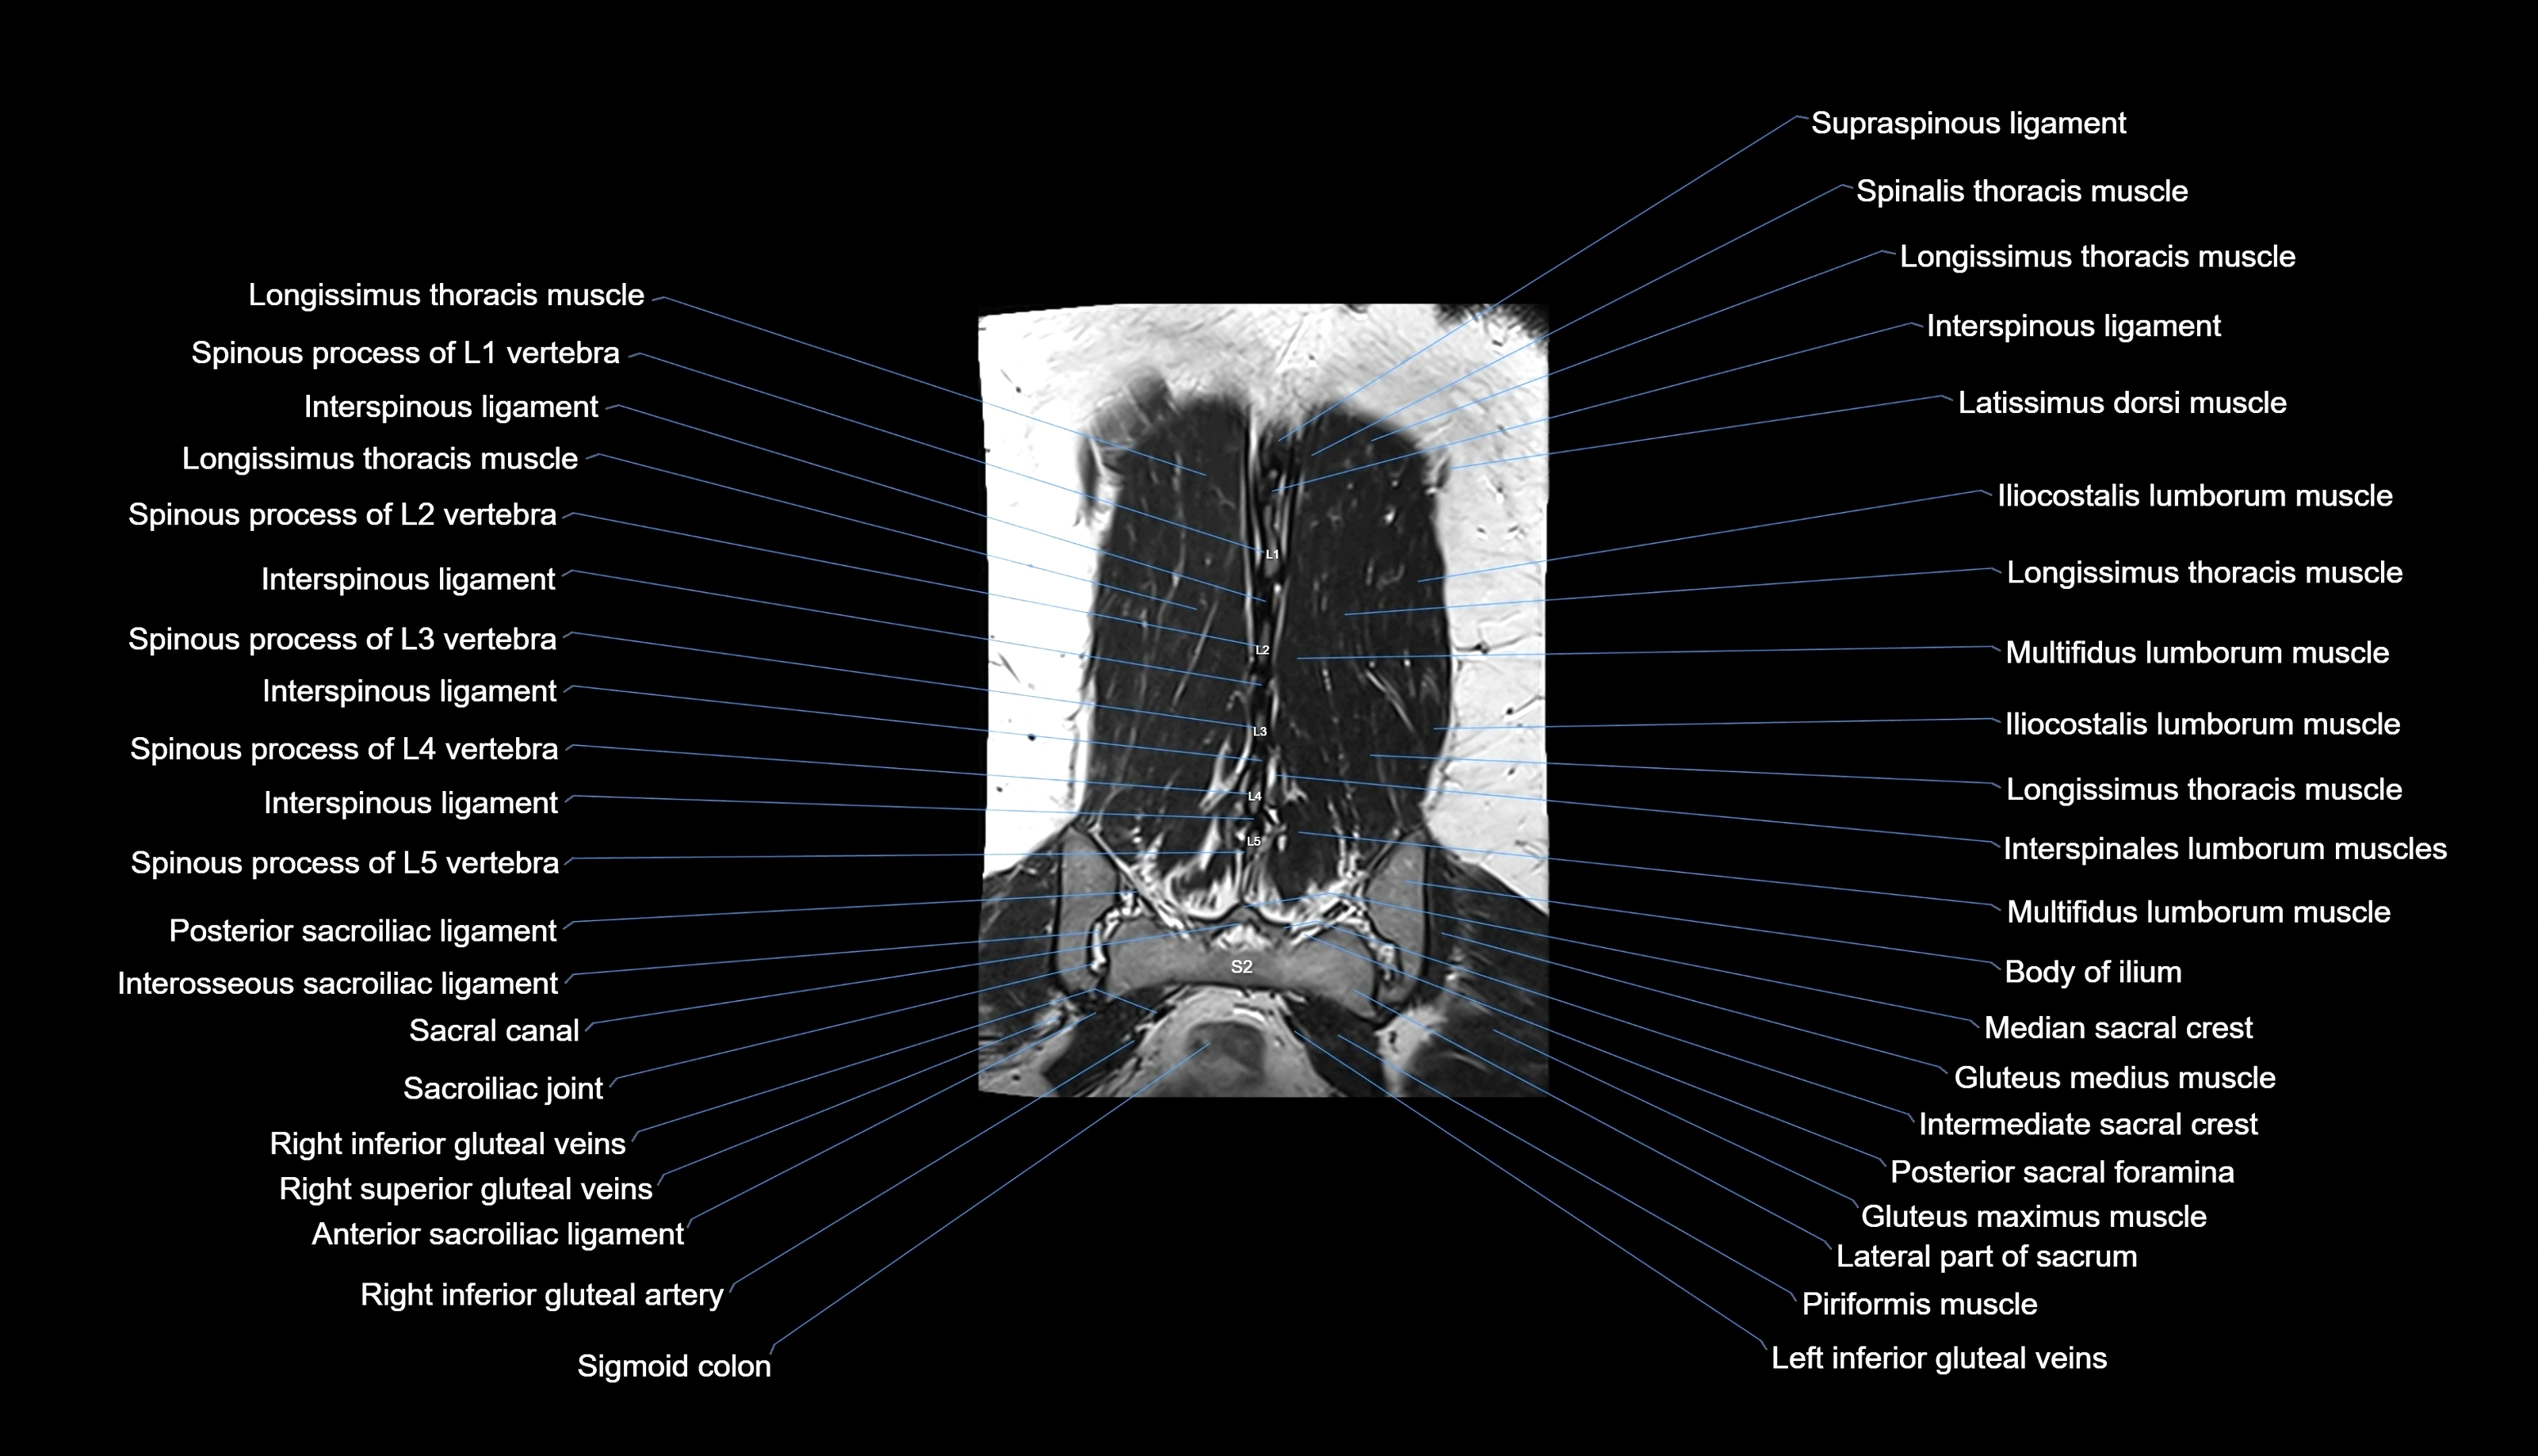

MRI images